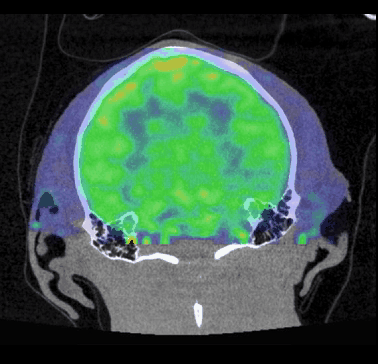

CASE 3: NHP brain PET/CT dynamic FDG imaging

workimg

• Courtesy of: CERMEP, Lyon, France

Research objective: Investigation of FDG uptake in NHP brain

Animal model: NHP, ~ 3 kg

Acquisition protocol: PET imaging: 60 min acquisition, injection right after acquisition starts. CT imaging: 80kV, 40s

Processing and reconstruction protocol: PET: 3D OSEM, 6x 10 min, 0.84 mm isotropic voxel size. CT: 0.15 mm isotropic voxel size

Biomarker or contrast agent: 18F-FDG, ~ 3 mCi